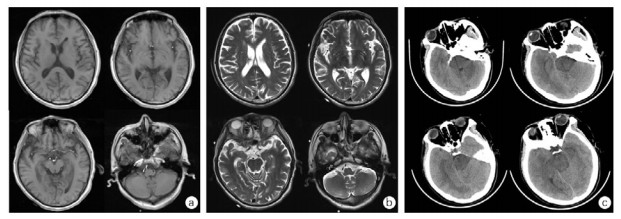

1 资料与方法 1.1 治疗经过病例1是一名70岁男性,因“口服甲维虫螨腈(甲氨基阿维菌素1%,虫螨腈5%)20 mL, 10 h”入院,虫螨腈含量1 g。患者自服杀虫剂5 h后在当地医院予清水500 mL催吐1次。摄入10 h后转至本院,入室查体:T 36.8℃,P 98次/min,R 20次/min,BP 138/83 mmHg,SpO2 97%,心肺腹部均无异常。初步诊断:急性杀虫剂中毒(虫螨腈)。给予乳果糖90 mL、复方聚乙二醇电解质散1 000 mL、20%甘露醇250 mL口服导泻,30%脂肪乳250 mL静脉滴注。摄入毒物后13 h、16 h、38 h、41 h、60 h、63 h共行6次(2次/ d×3 d)血液灌流,动态监测血液中虫螨腈及代谢产物溴代吡咯腈浓度(见图 1A)。摄入毒物后185 h,患者出现一过性体温升高,最高38.0℃(见图 2A),并伴有四肢肌张力增高。第9天患者自动出院,出院后3 d随访无异常,其后失访(通过多种方式未查证到患者死亡信息)。在入室、首次血液灌流1 h、2 h、12 h后,以及灌流3次后、入室第5天、第7天共7个时间点,分别留取EDTA抗凝血2 mL。(住院期间实验室检查见表 1,颅脑影像学检查见图 3A、B)。

| 摄入虫螨腈后131 h病例1颅脑磁共振T1WI(A)、T2WI(B):两侧大脑半球对称,灰白质对比良好,两侧侧脑室旁多发小片状长T1、长T2信号。摄入虫螨腈后230 h病例2颅脑CT图像(C):脑干密度减低,脑白质水肿,全脑肿胀 图 3 摄入虫螨腈后患者颅脑影像学检查 Fig 3 Cerebral imaging of patients after ingestion of chlorfenapyr |

病例2是一名40岁女性,因“口服虫螨腈虱螨脲(虫螨腈9.5%,虱螨脲2.5%)250 mL 149 h”入院,虫螨腈含量23.75 g。患者自服杀虫剂后家属立即予以催吐1次,摄入毒物后2 h即感全身燥热、多汗。患者拒绝洗胃,当地医院未予特殊治疗。149 h后转至本院,入室查体:T 36.5℃,P 75次/min,R 18次/min,BP 99/67 mmHg,SpO2 98%,神志清楚,心肺腹部均无异常。初步诊断:急性杀虫剂中毒(虫螨腈)。予30%脂肪乳250 mL静脉滴注、血液灌流2次/ d×2 d共4次、持续性血液透析滤过(continuous veno-venous hemodiafiltration, CVVHDF)治疗85 h,动态监测血液中虫螨腈及溴代吡咯腈浓度(见图 1B)。摄入毒物203 h患者出现烦躁、谵妄,230 h转为昏迷状态。237 h患者突发呼吸停止,血压下降至54/36 mmHg,双瞳直径散大至3.5 mm,立即予经口气管插管、机械通气,同时积极抗休克治疗,血压难以维持,患者于摄入247 h后死亡。在入室、首次血液灌流后、第二次灌流后,发病第7、8、9天的6:00和18:00共9个时间点,分别留取EDTA抗凝血2 mL。(住院期间实验室检查见表 1,颅脑影像学检查见图 3C)。

急性虫螨腈中毒的诊断主要根据病史和临床表现。经消化道摄入虫螨腈导致中毒的个案报告中,可将病程分为早期(1~7 d):患者表现为自感体热、出汗多、乏力等症状,实验室检查可提示肌酸激酶、谷草转氨酶的升高。后期(7~14 d)患者可出现神经系统症状,例如烦躁不安、视物模糊等、昏迷和肌张力增高,并出现高热,因患者体温可上升至42℃,有些文献称之为“恶性高热”[4-8]。头颅影像学检查可出现脑白质水肿、脑干低密度影,全脑肿胀等[9]。死亡常可表现为突发的持续肌张力增高、心搏骤停且难以进行心肺复苏[4, 10],超高热至死亡常仅有数小时的间隔[7]。